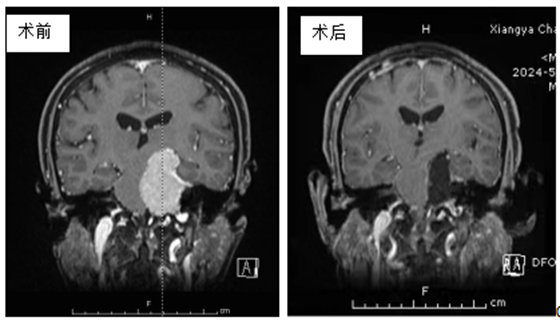

今年72岁的宋奶奶于半年前无明显诱因下出现左侧耳鸣伴听力减退,当时未予重视,3周前耳鸣加重,在当地通过头颅MRI检查,竟然发现了宋奶奶颅内左侧桥小脑角区见一团块状占位性病变,约...